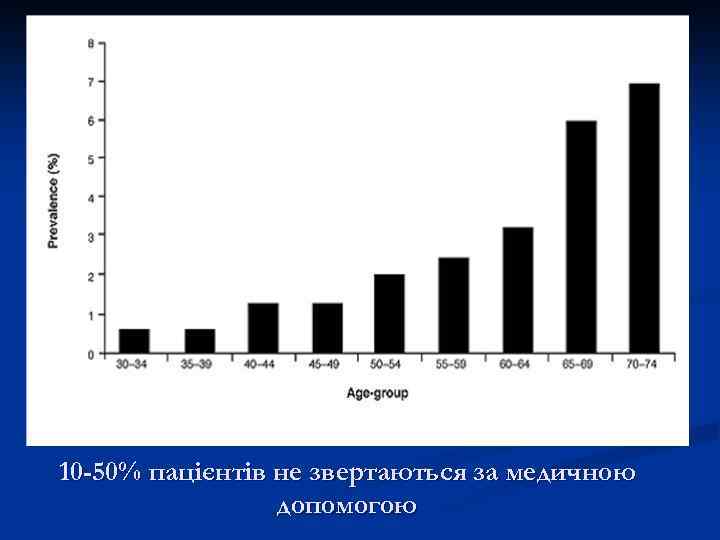

10 -50% пацієнтів не звертаються за медичною допомогою

10 -50% пацієнтів не звертаються за медичною допомогою

Частота оклюзивних захворювань артерій нижніх кінцівок у старшій віковій групі може сягати 23%, серед яких у 20 -40% розвивається ХКІНК (Management of Peripheral Disease (РАD), Trans Atlantic Inter–Society Working Group (ТАSС), 2000), досягаючи 600 -800 на 1 млн. жителів (Critical limb ischaemia: comments on consensus document, 1991).

Частота оклюзивних захворювань артерій нижніх кінцівок у старшій віковій групі може сягати 23%, серед яких у 20 -40% розвивається ХКІНК (Management of Peripheral Disease (РАD), Trans Atlantic Inter–Society Working Group (ТАSС), 2000), досягаючи 600 -800 на 1 млн. жителів (Critical limb ischaemia: comments on consensus document, 1991).